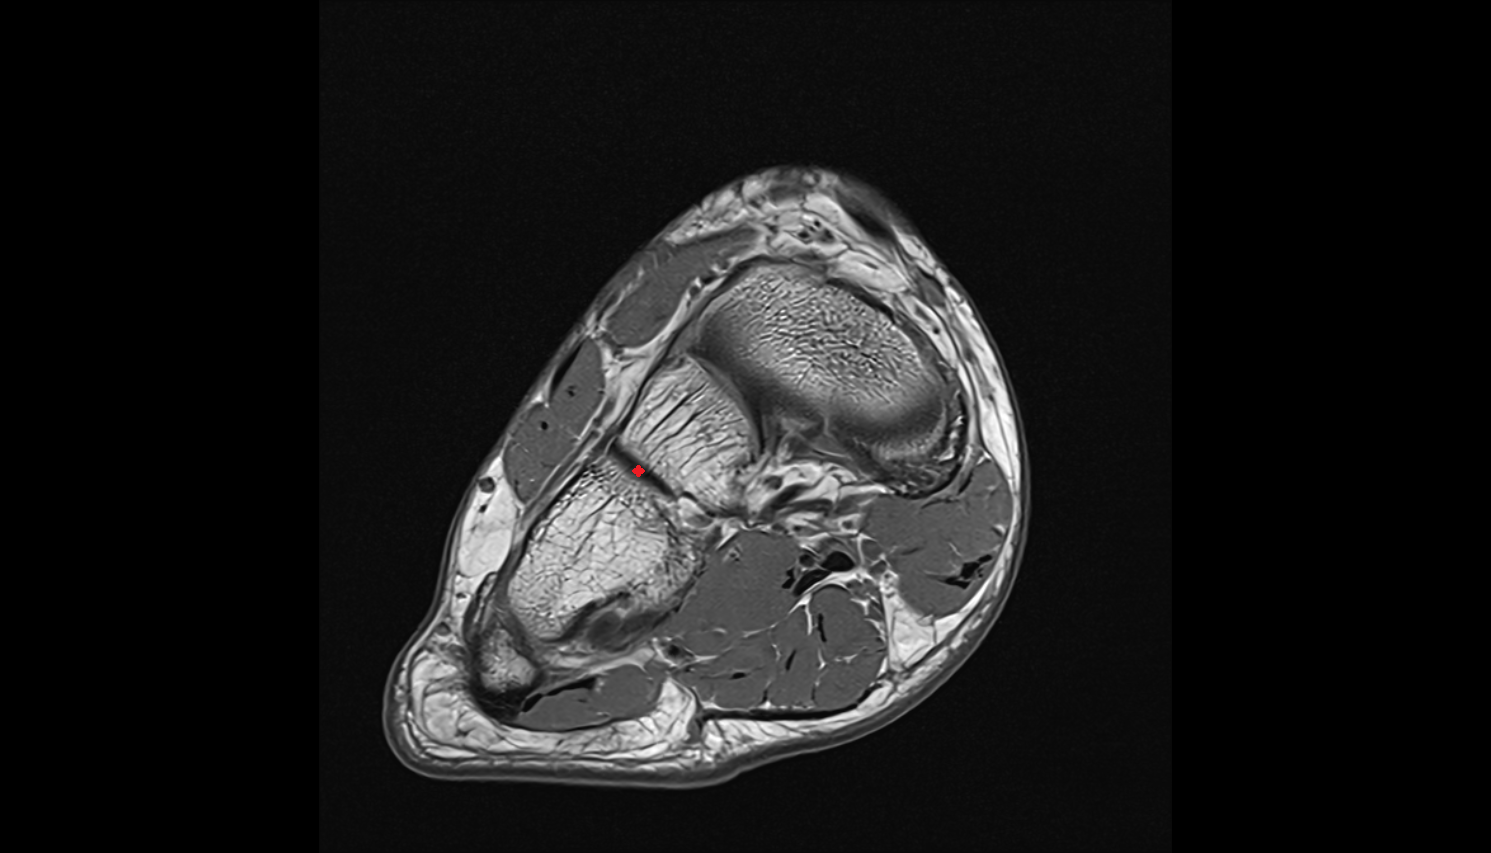

- Talus

- Body of talus

- Calcaneus

- Sustentaculum tali

- Medial malleolus

- Lateral malleolus

- Ankle joint

- Tibialis posterior muscle

- Flexor digitorum longus muscle

- Flexor hallucis longus muscle

- Tibialis posterior tendon

- Flexor digitorum longus tendon

- Flexor hallucis longus tendon

- Achilles tendon